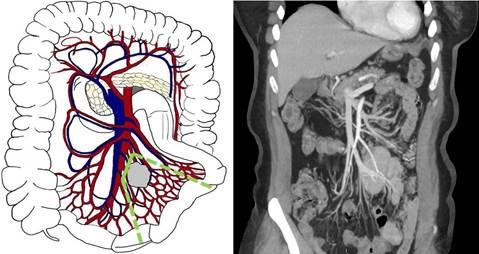

Второй тип (уровень II по Ohrvall) - локализация конгломерата в зоне отхождения a. et v. Ileocolica. Такая картина часто наблюдается при локализации опухоли в терминальном отделе подвздошной кишки. При этом типе выполняется перевязка этих сосудов у их основания с сохранением ствола верхней брыжеечной артерии (ВБА) и верхней брыжеечной вены (ВБВ) ниже. Такой подход предполагает выполнение илеоцекальной резекции или гемиколэктомии справа в зависимости от локализации первичной опухоли и возможности сохранения правых толстокишечных сосудов (рис. 2).

Рис. 2. Второй тип (уровень II) - поражение подвздошно-ободочной артерии или вены